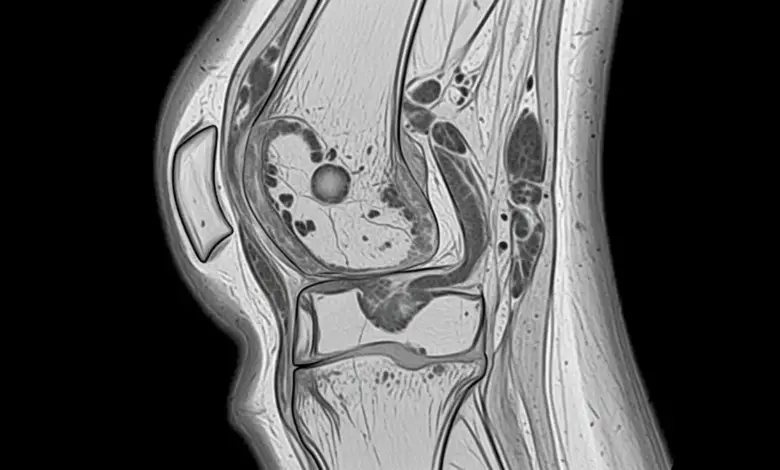

Exames de imagem podem entrar como apoio.

- Radiografias ajudam a checar alinhamento, presença de ossificações e outras alterações ósseas.

- A ressonância magnética pode contribuir quando existe suspeita de lesões associadas e para organizar o plano de tratamento.